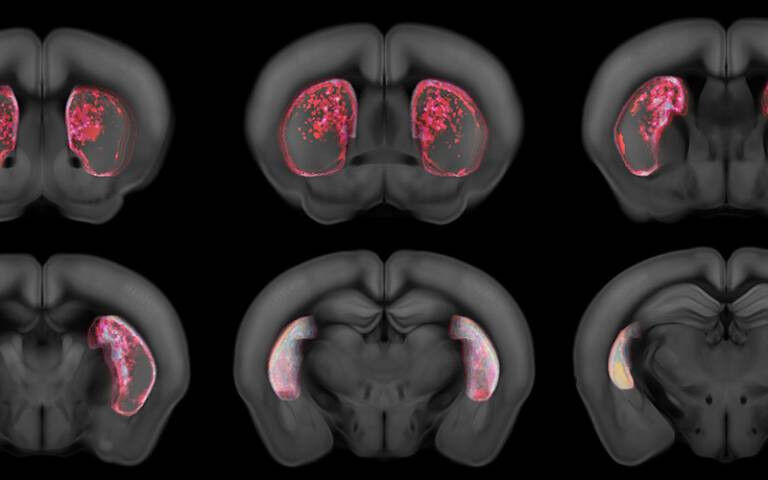

RPE neurons project to all’areas of a brain region called the striatum (a critical component of the movement control and reward systems) apart from one, called the tail of the striatum, whereas the movement-specific neurons project to all’areas apart from the nucleus accumbens. This suggests that the nucleus accumbens exclusively signals reward, and the tail of the striatum exclusively signals movement.

By investigating the tail of the striatum, the team were able to isolate the movement neurons and discover their function. To test this, the researchers used an auditory discrimination task in mice, which was originally developed by scientists at Cold Spring Harbor Laboratory in the US. Co-first authors Dr Francesca Greenstreet, Dr Hernando Martinez Vergara and Dr Yvonne Johansson used a genetically encoded dopamine sensor, which showed that dopamine release in this area was not related to reward, but it was related to movement.

To further understand this, the team silenced the tail of striatum in expert mice and found that this had a catastrophic effect on their performance in the task. This showed that while in early learning animals form a preference using the value-based system based on RPE, in late learning they switch to exclusively use APE in the tail of striatum to store these stable associations and drive their choice. The team also used extensive computational modelling, led by Dr Claudia Clopath at UCL, to understand how the two systems, RPE and action prediction error, learn together.